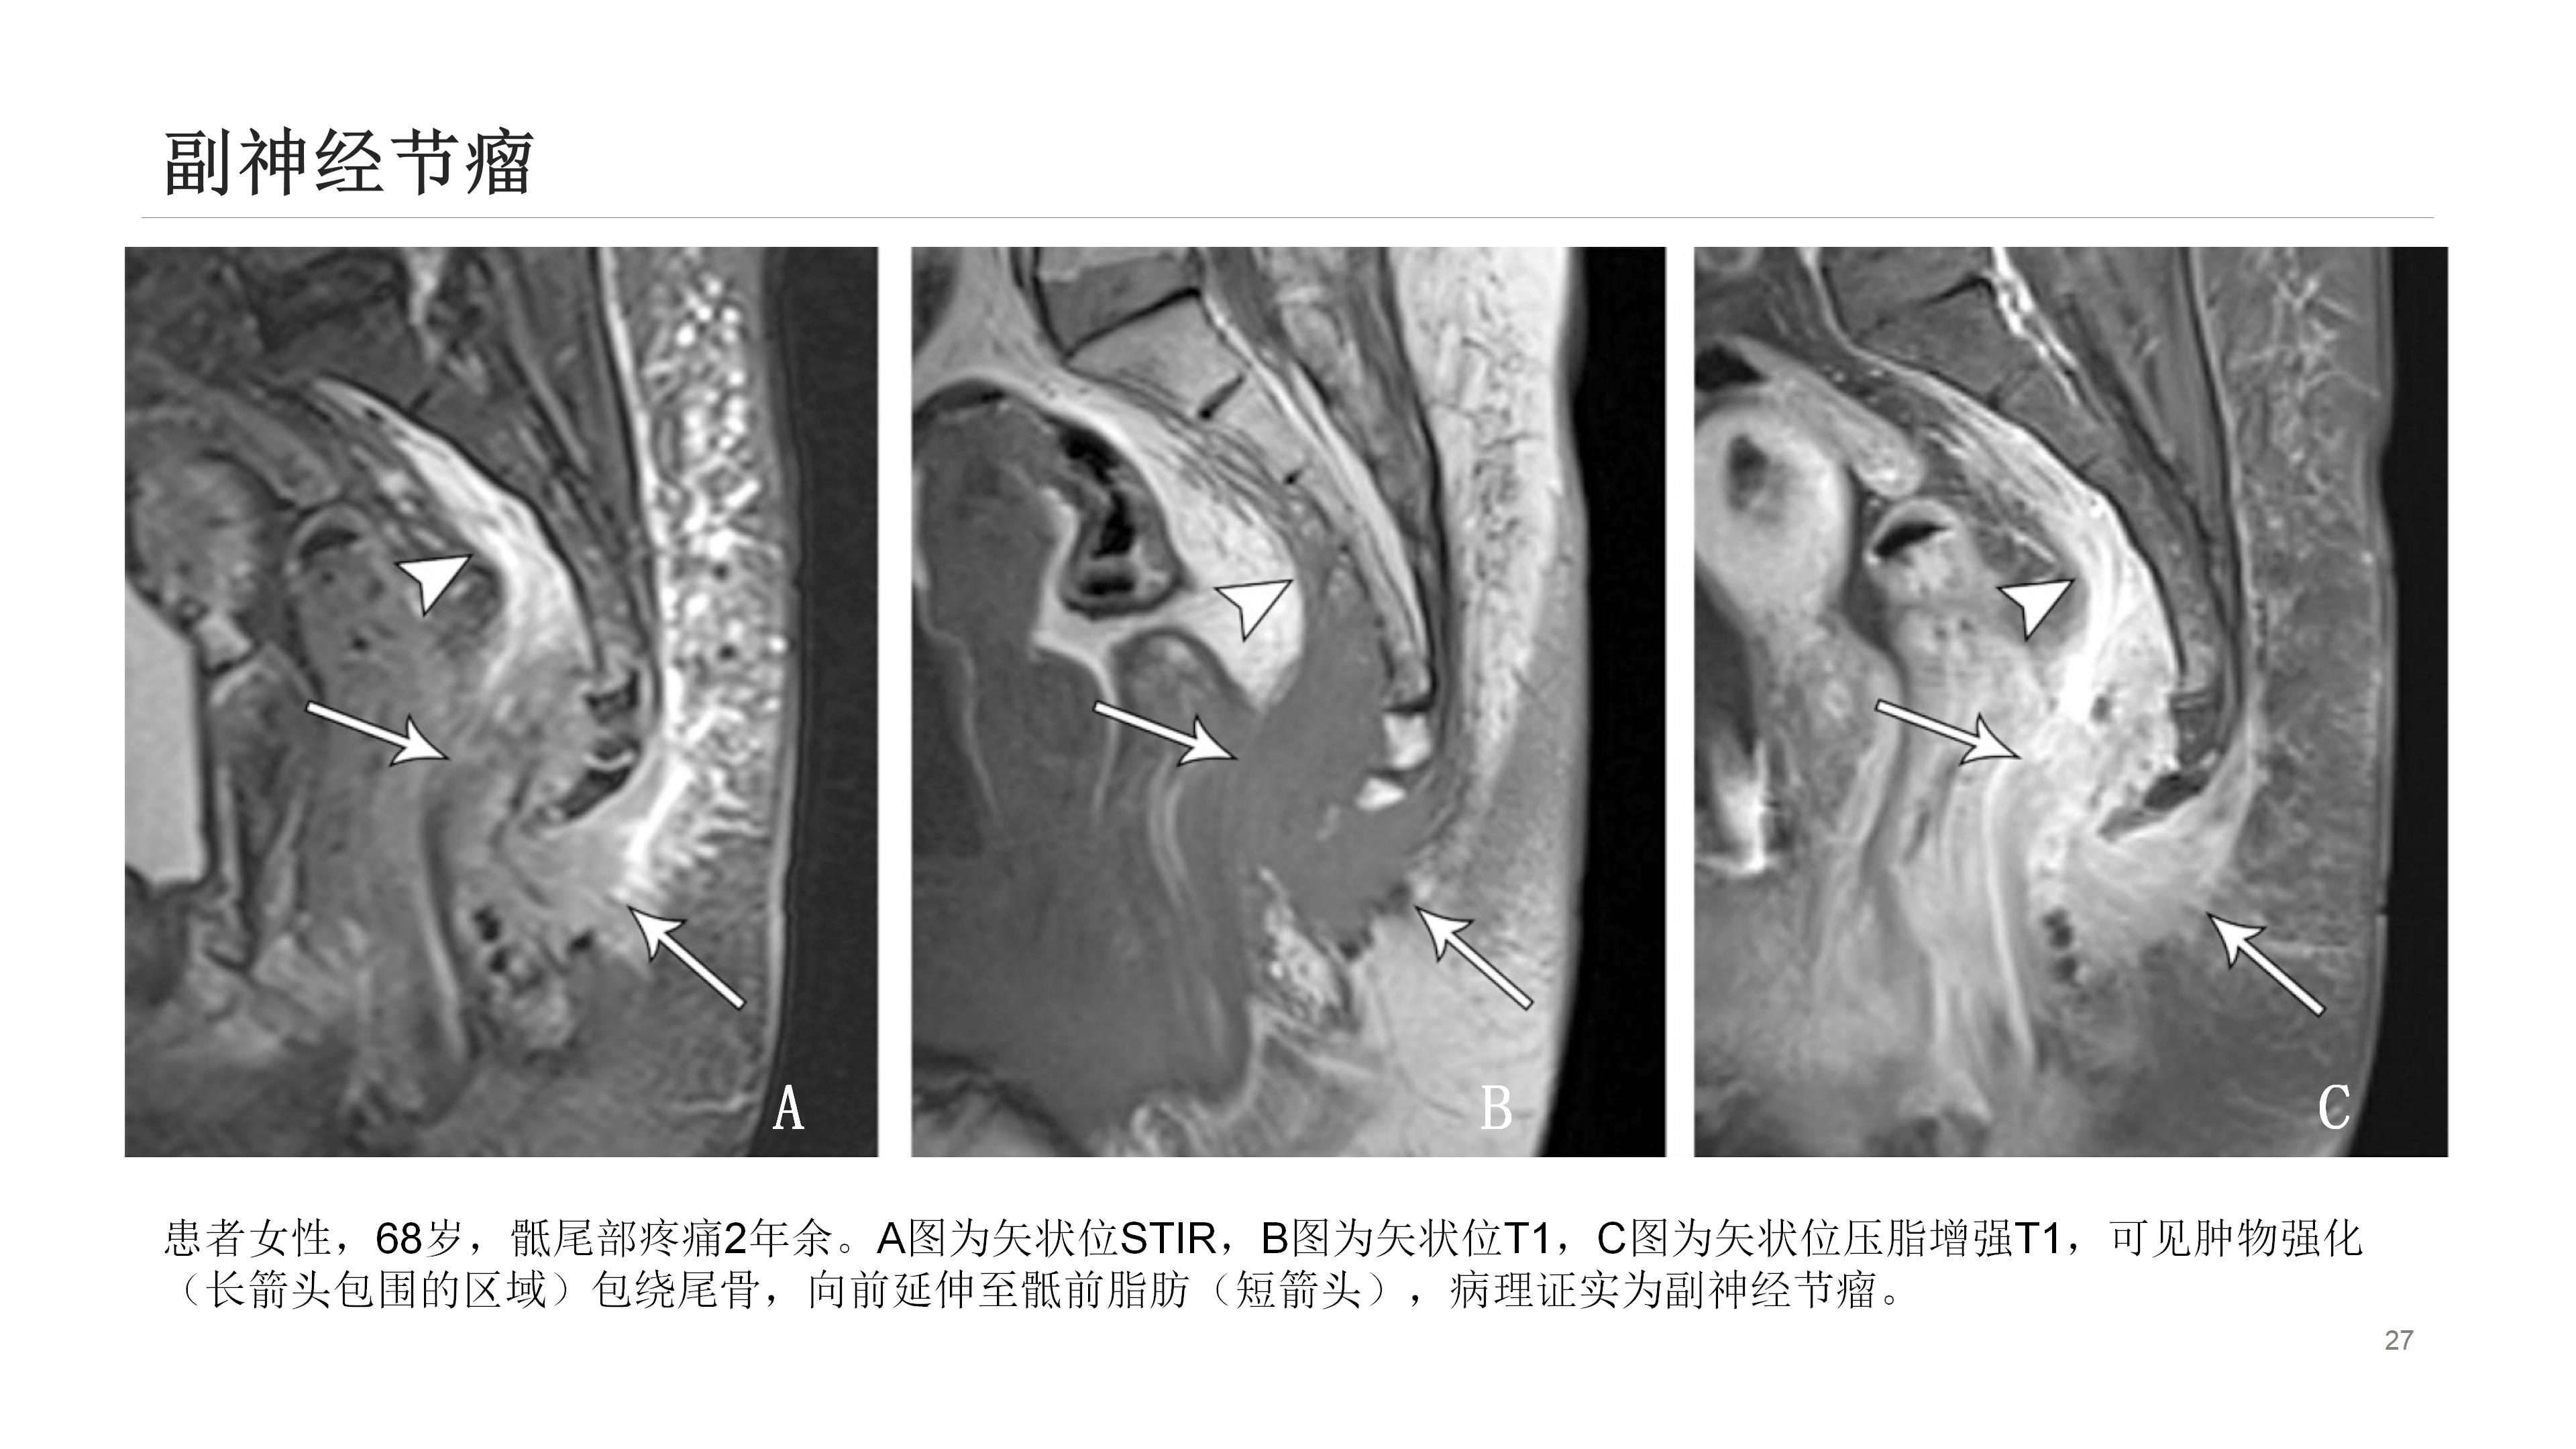

此外,诸如肿瘤、感染、晶体沉积病、囊肿形成(如藏毛囊肿)等其他疾病也可导致尾骨疼痛。